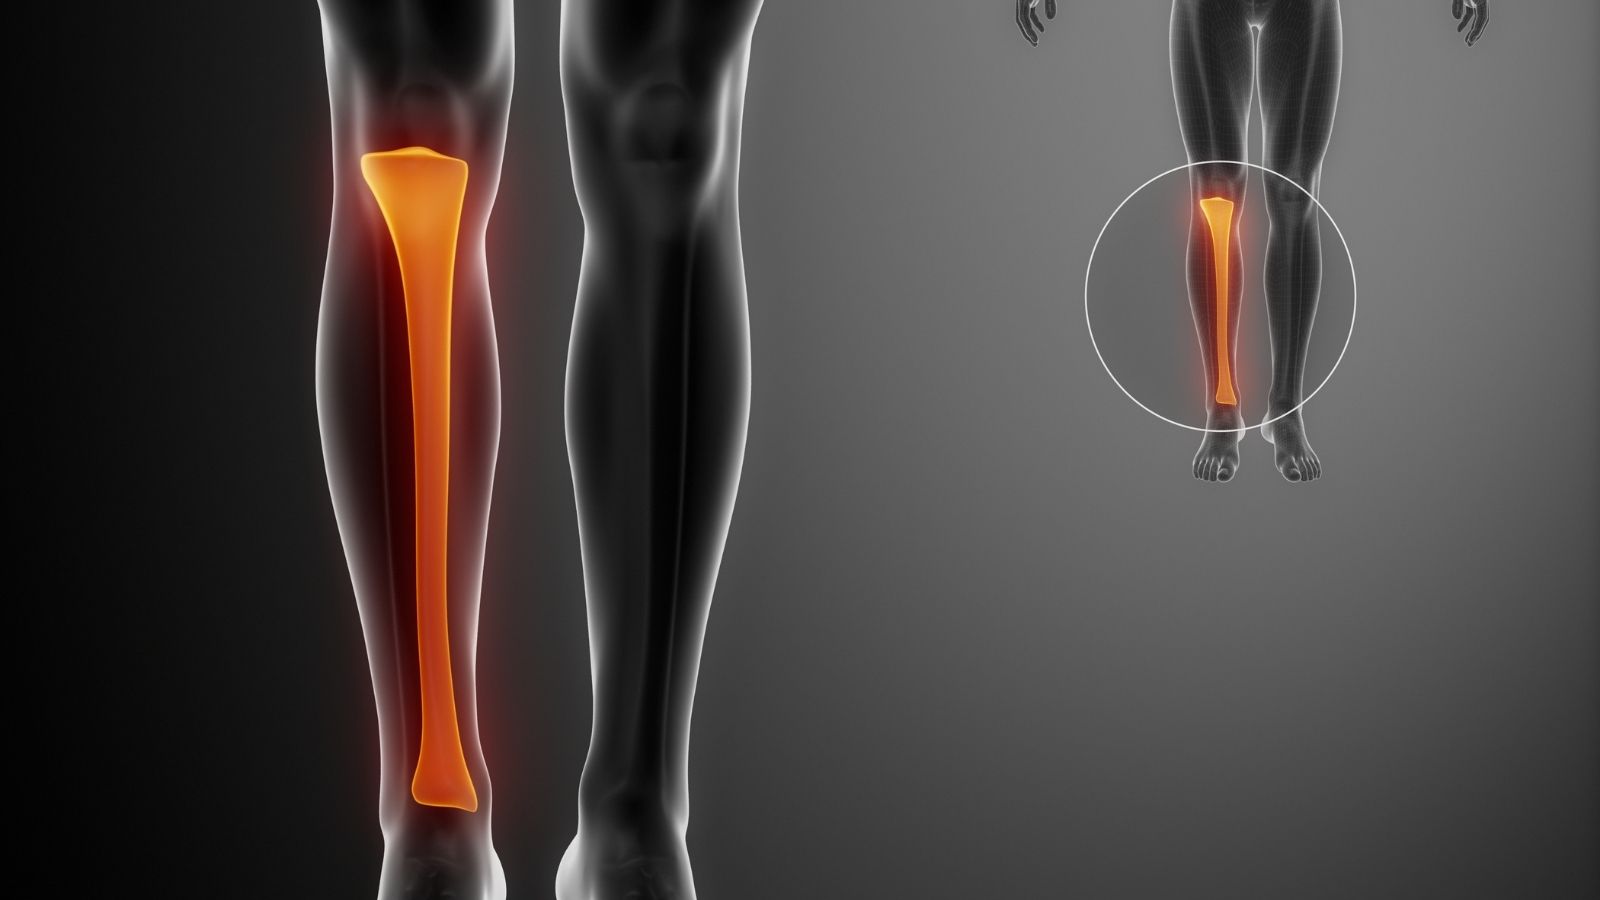

Anatomik yapımızı incelediğimizde, diz ile ayak bileği arasında iki adet kemik olduğunu görürüz. Bunlardan daha kalın olanı, iç tarafta yer alan ve vücut ağırlığımızın büyük bir kısmını taşıyan kaval kemiği, yani tibiadır. Dış tarafta yer alan, daha ince ve zarif yapıdaki kemik ise fibula, yani baldır kemiğidir. Fibula, yukarıda diz ekleminin hemen altına tutunurken, aşağıya doğru indikçe ayak bileğinin dış tarafındaki o sert çıkıntıyı oluşturur. Bu çıkıntıya tıp dilinde “lateral malleol” adını veriyoruz.

Pek çok hasta, bu kemiğin ince olması sebebiyle vücut için çok da elzem olmadığını düşünür. Hatta bazen “yedek parça” gibi algılandığına şahit olurum. Ancak bu düşünce biyomekanik açıdan oldukça yanlıştır. Evet, fibula üzerine binen yük miktarı kaval kemiğine göre çok daha azdır. Yürürken vücut ağırlığınızı direkt olarak bu kemik taşımaz. Fakat fibulanın görevi yük taşımaktan ziyade, denge ve stabilite sağlamaktır.

Ayak bileği eklemini bir marangozun yaptığı zıvana geçme sistemine benzetebiliriz. Kaval kemiği (tibia) tavanı ve iç duvarı oluştururken, baldır kemiği (fibula) dış duvarı oluşturur. Bu iki kemik, aralarındaki güçlü bağlar sayesinde bir arada durarak, ayak bileği kemiğinin (talus) içinde hareket edeceği yuvayı meydana getirir. Eğer fibula kırılırsa veya yerinden oynarsa, bu yuvanın dış duvarı yıkılmış demektir. Duvar yıkıldığında, içerideki talus kemiği serbest kalır ve sağa sola çarpmaya başlar. Bu nedenle fibula, ayak bileğinin kilit taşıdır diyebiliriz. Onun sağladığı destek olmadan düzgün bir yürüyüşten veya ağrısız bir basmadan söz etmek mümkün değildir.